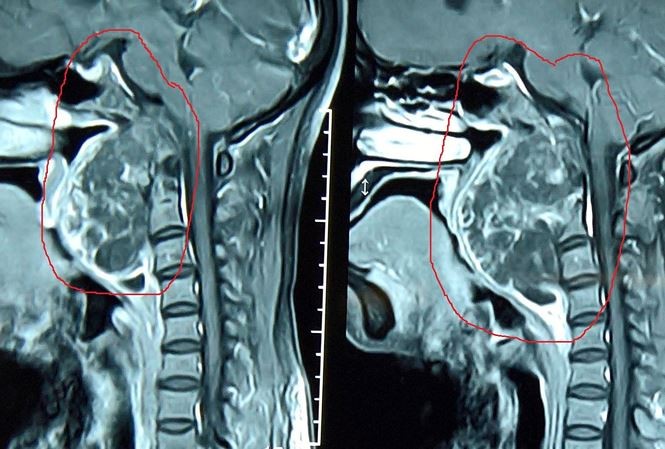

Khối u nằm vắt từ nền sọ xuống cột sống qua hình chụp x- quang.

Các bác sĩ khoa Ung bướu và phẫu thuật Đầu cổ, BV Tai Mũi Họng trung ương vừa phối hợp với các bác sĩ khoa Ngoại thần kinh BV Bạch Mai phẫu thuật thành công cho một bệnh nhân có khối u rất đặc biệt và nguy hiểm.

PGS.TS Lê Minh Kỳ, Trường khoa Ung bướu và phẫu thuật đầu cổ, BV Tai Mũi Họng TƯ cho biết, bệnh nhân là N.T.L 52 tuổi ở Nghệ An. Bệnh nhân bị u nguyên sống, một bệnh lý ác tính do tế bào “còn sót lại” trong bào thai. Tế bào này cứ sống chung như vậy qua thời gian dài và nó sẽ dần dần lớn lên trở thành ác tính. Do đó không có triệu chứng đặc hiệu cũng như bệnh không thể phòng chống.

Cũng theo PGS. Kỳ, u nguyên sống là một loại ung thư xương được tìm thấy trong hộp sọ và cột sống. U hay bị nhầm với u amidan hoặc u bên họng. Tỷ lệ để mắc loại ung thư này là 1/ 1 triệu người.

U nguyên sống phát triển từ tàn tích rất nhỏ của sụn khớp và có thể người bệnh đã mang nó từ trong bụng mẹ. Bởi vì rất hiếm, nên u nguyên sống ít được nghiên cứu, nhưng các chuyên gia có thể loại bỏ nguyên nhân di truyền khỏi loại ung thư này.

Với bệnh lý phức tạp như trên, ca mổ tiên lượng 50/50, bởi nếu phẫu thuật viên chỉ sơ xuất chút nếu động vào động mạch cảnh, hoặc làm tổn thương tủy sống, máu sẽ phun không cầm được, bệnh nhân có thể liệt tứ chi, thậm chí tử vong ngay trên bàn mổ.